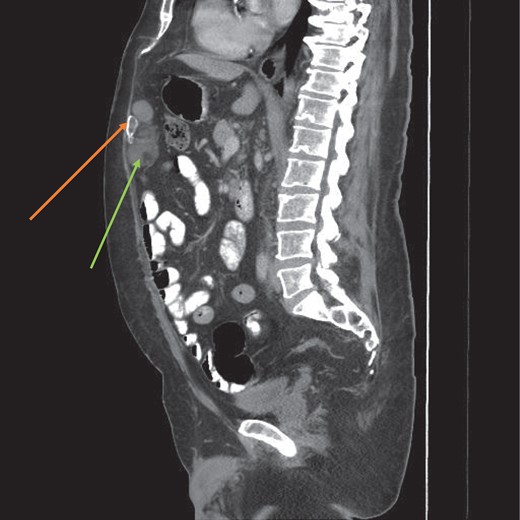

His medical history was significant for hypertension and alchoholism and both were well controlled. Radiological imaging included a computerized tomography (CT) scan which reported an internal hernia in the epigastrium (Figs 1 and 2). There were no radiological signs of bowel strangulation.

CT scan sagittal view of the myelolipoma (green arrow) with a calcified component (orange arrow).

CT scan axial view of the myelolipoma (green arrow) with calcification (orange arrow). Abdominal wall musculature is intact thereby excluding an incisional hernia.

This was an incidental diagnosis based on a misinterpretation of the patient’s radiological imaging. Upon further discussion with our radiology colleagues, there was a consensus view that this was indeed a soft tissue tumour of the abdominal wall and not an internal hernia as originally reported. The author himself felt that this was an incisional hernia prior to surgery based on his clinical examination and original CT findings. Diastasis recti of the rectus abdominus musculature may also have contributed to the clinical confusion of an incisional hernia (Fig. 2). Given the rarity of this tumour, a soft tissue lesion was not entertained as an initial diagnosis.